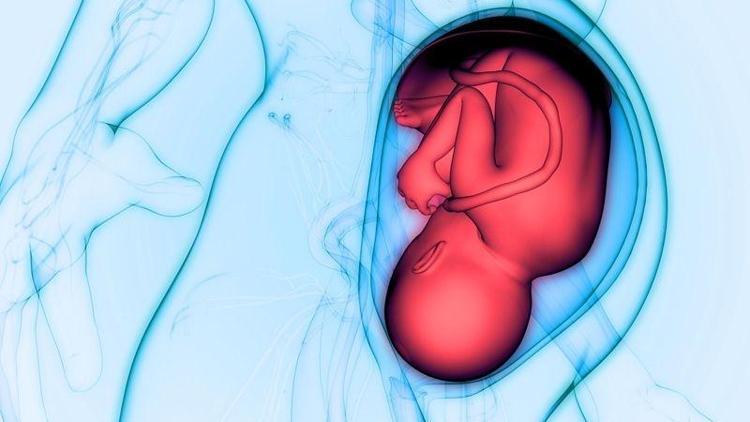

Bu hafta bebeğinizin kilosu yaklaşık olarak 1000 gram, boyu ise 36 cm civarındadır. Gözlerini kırpabilir, böylece kirpiklerini hareket ettirir. Görme gelişimiyle birlikte rahime doğru gelen ışığı görebilir. Beyninde milyarlarca sinir hücreleri oluşur ve kendini dış dünyaya hazırlamak için kilo almaya başlar.

Bebeğiniz yaklaşık olarak 38 cm boyunda, 1350 gram ağırlığındadır. Bebeğinizin çevresinde amniyotik sıvı olacak fakat bu sıvının hacmi bebeğiniz büyüyüp rahimde daha çok yer kaplamaya başladığında azalacaktır.

Görme duyusu gelişmiş fakat hala çok keskin değildir. Doğduktan sonra bile gözlerini belli bir süre kapalı tutacaktır. Gözlerini açtığında ışık farklılığına cevap verecek fakat 20/400 görme yetisine sahip olacaktır. Bu da demek oluyor ki, sadece yüzünden birkaç cm uzaklıktaki cisimleri seçebilir (Normal yetişkin görüşü i20/20).